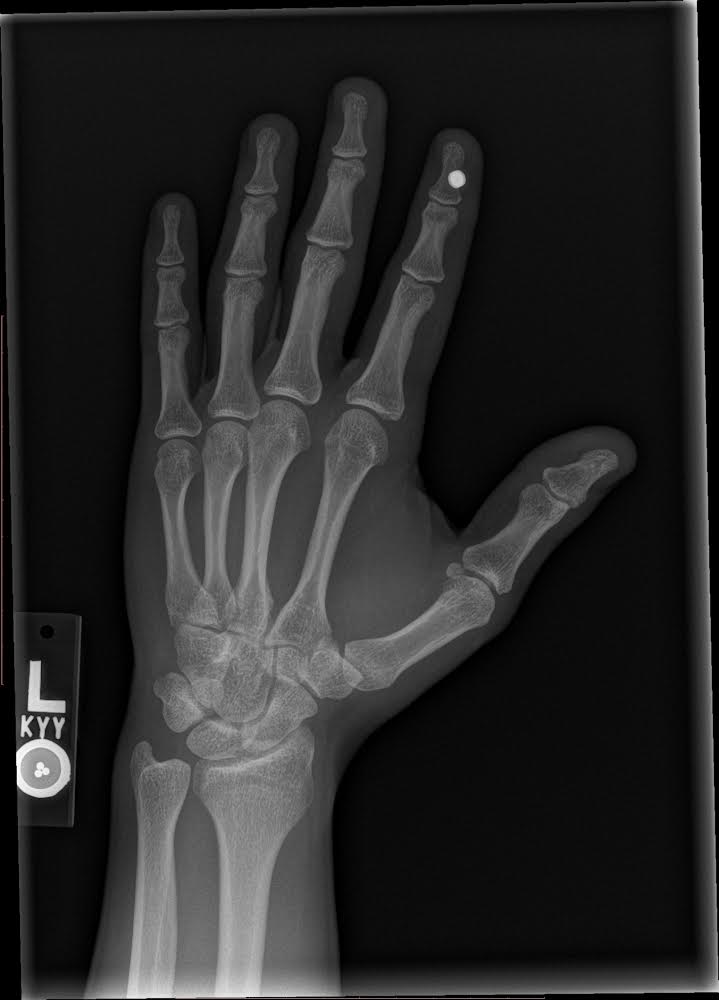

Little Titan update: approaching 2 years with it in and no complaints so far. Nothing strange has happened with it. I’ve bumped it causing significant pain two or three times over the years but I’d compare them to a bad toe stubbing. Painful for a minute, then sore fore less than a day. I can say the sensitivity has slightly decreased since the first 6 months but I suspect my healing tissue was just more sensitive than current tissue. I can still feel the magnets in the airood case in my left pocket as my hand swings by my leg while I walk (that’s one of my favorite things). Here are some x-rays I got this year of both my titan and my NExT installs. NExT chip was installed by a nurse I know Thanksgiving of 2022. No numbing, but the back of the hand wasn’t a very painful place and it went smooth and well.